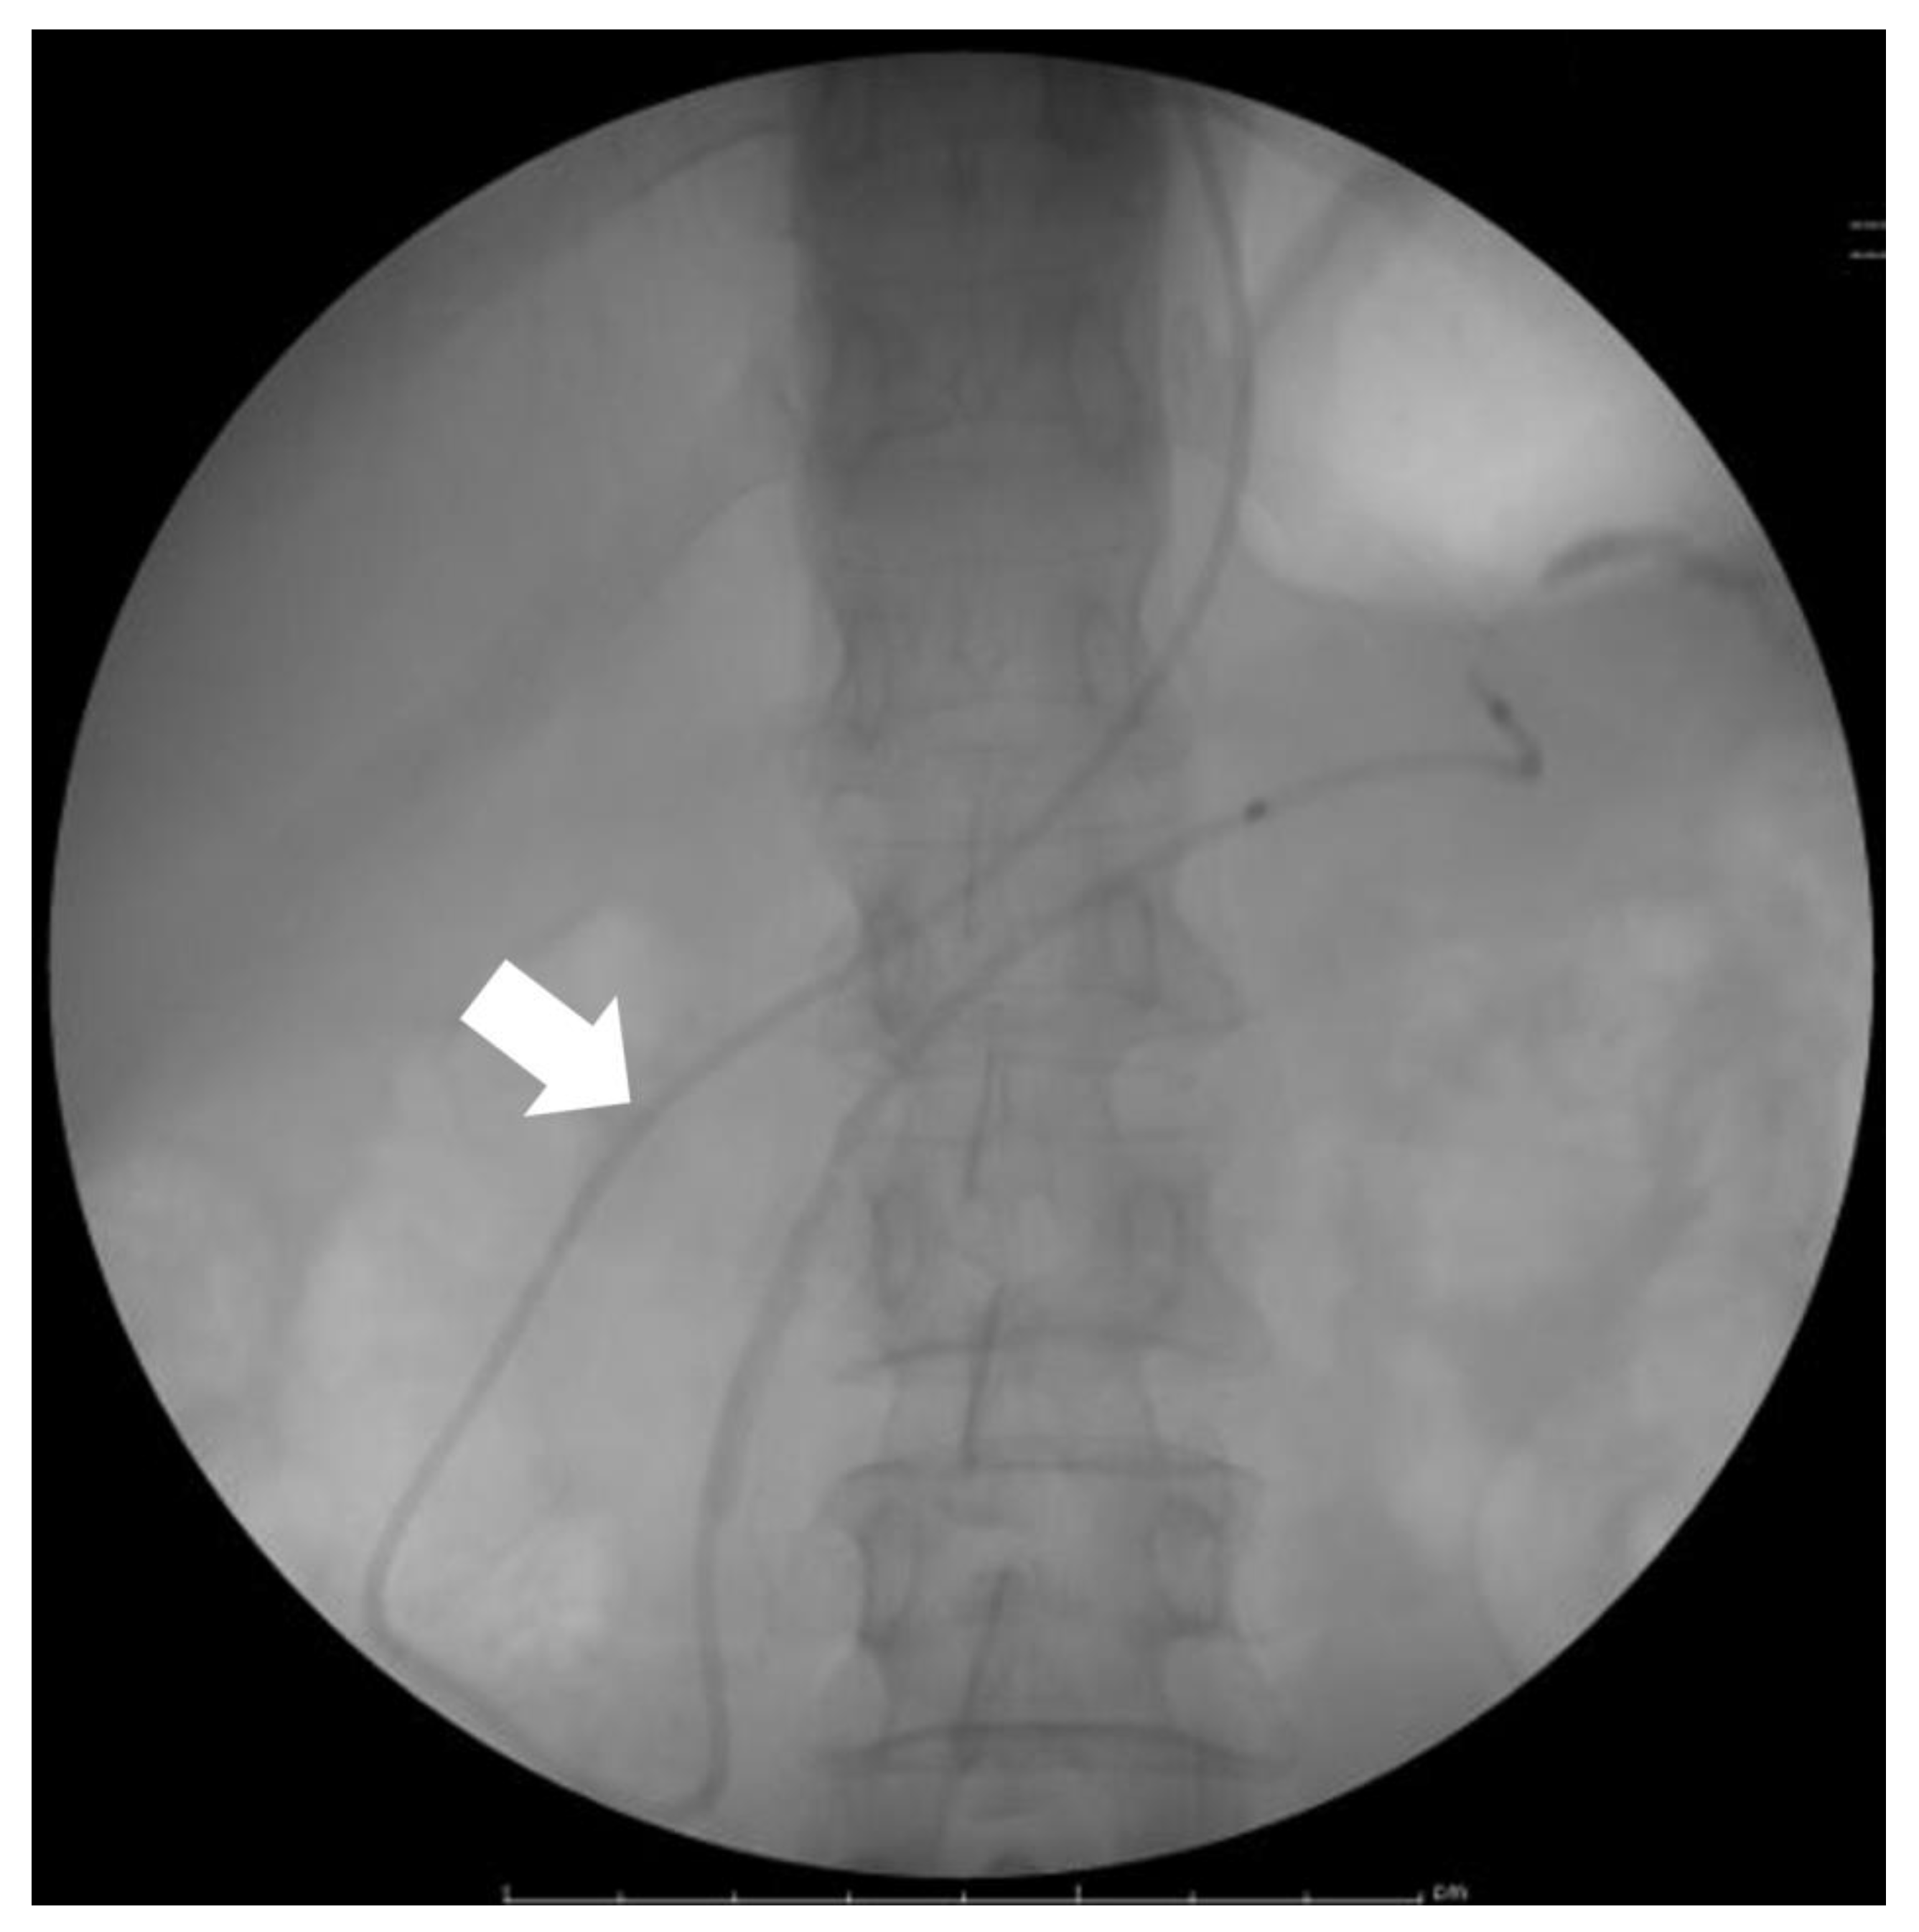

- Iiboshi, T.; Hanada, K.; Fukuda, T.; Yonehara, S.; Sasaki, T.; Chayama, K. Value of Cytodiagnosis Using Endoscopic Nasopancreatic Drainage for Early Diagnosis of Pancreatic Cancer: Establishing a New Method for the Early Detection of Pancreatic Carcinoma In Situ. Pancreas 2012, 41, 523–529. [Google Scholar] [CrossRef]

- Satoh, T.; Kikuyama, M.; Kawaguchi, S.; Kanemoto, H.; Muro, H.; Hanada, K. Acute Pancreatitis-Onset Carcinoma In Situ of the Pancreas with Focal Fat Replacement Diagnosed Using Serial Pancreatic-Juice Aspiration Cytologic Examination (SPACE). Clin. J. Gastroenterol. 2017, 10, 541–545. [Google Scholar] [CrossRef] [PubMed]

- Kikuyama, M.; Kamisawa, T.; Kuruma, S.; Chiba, K.; Kawaguchi, S.; Terada, S.; Satoh, T. Early Diagnosis to Improve the Poor Prognosis of Pancreatic Cancer. Cancers 2018, 10, 48. [Google Scholar] [CrossRef]